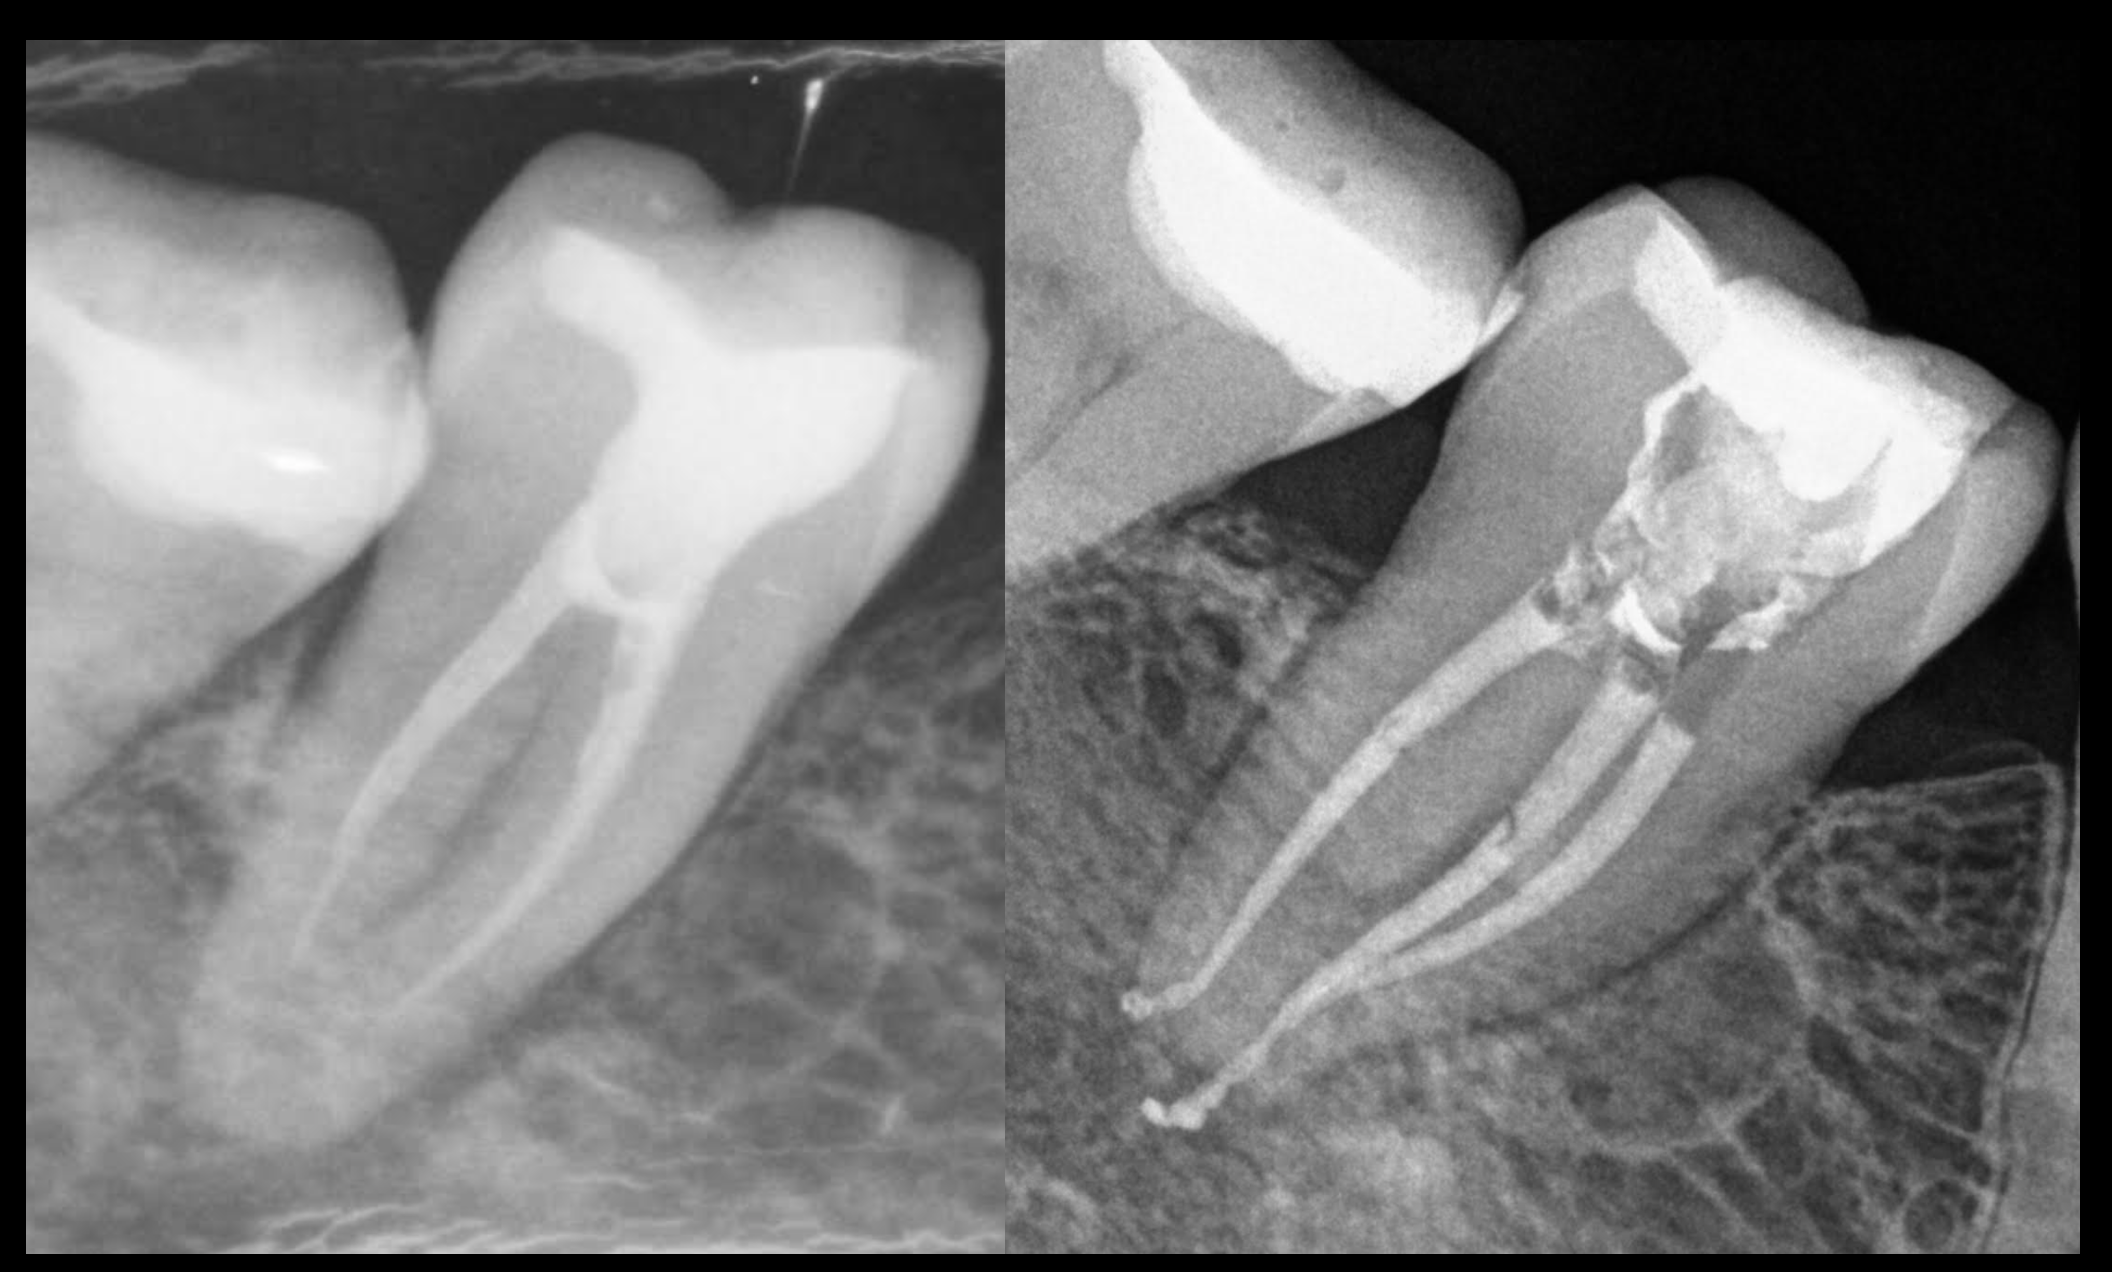

Radiodiagnóstico y Microscopio

Todos nuestros tratamientos están realizados con Microscopio.

Tenemos la más alta tecnología de radiodiagnóstico.

Nuestro CBCT consigue alta resolución para la odontología multidisciplinar, Endodoncia, Implantología, Ortodoncia, Cirugía Maxilofacial.

Generamos Hueso

Generamos hueso sin cirugía.

El tratamiento de conductos consigue regenerar el hueso perdido y con ello salvamos el diente del paciente.